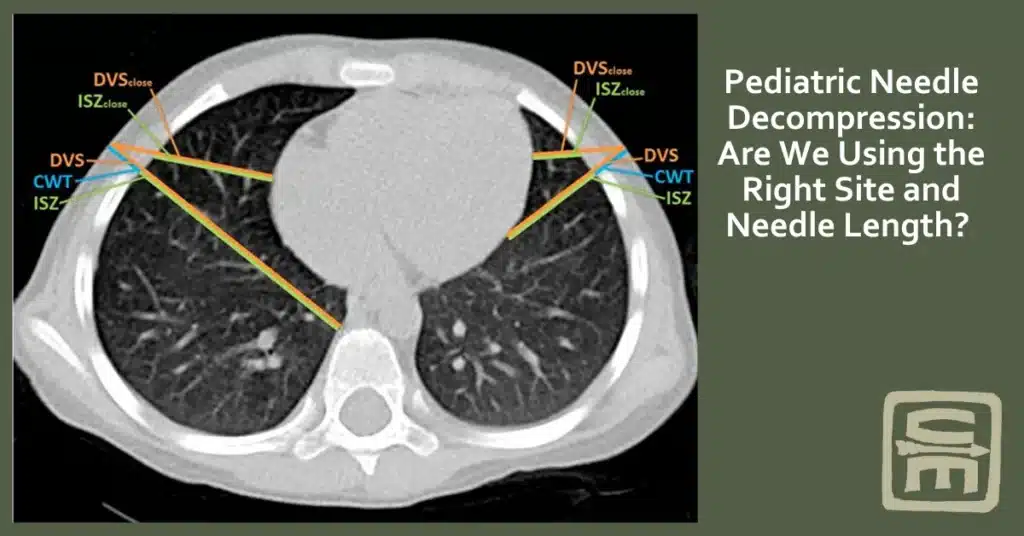

While adult guidelines for needle decompression for tension pneumothorax are well established, pediatric-specific recommendations remain an evolving discussion. Recent studies using CT and ultrasound have refined our understanding of pediatric chest wall thickness and the depth to vital structures

A retrospective study of 250 children under 13 years old undergoing chest CT measured chest wall thickness (CWT) at two key locations: the 2nd intercostal space (ICS), mid-clavicular line (MCL), and the 4th ICS, anterior axillary line (AAL).

However, some authors have also questioned the generalizability of CT chest data as most children don’t undergo CT imaging with its substantial radiation exposure. Additionally, for optimal CT imaging, children are placed with their arms up over their heads, which might reduce the thickness of their anterior chest wall because of the extension of the pectoralis major musculature in this position.

A convenience sample of 139 children, aged 10 years old and under undergoing chest CT, had the thickness of their chest walls measured at the 2nd intercostal space (ICS) mid clavicular line (MCL) and 4th ICS anterior axillae line (AAL) and also the depth to vital structures (DVS) within the chest at those locations. Vital structures were defined as the pericardium, aorta, superior vena cava, inferior vena cava, thymus gland, and pulmonary vessels segmental or larger.

Notably, the thymus and heart were directly adjacent to the chest wall at the 2nd ICS MCL in several children aged 0 and 5 years. As a result, the study authors recommended the 4th ICS AAL as the preferred site for pediatric needle decompression. However, they also found that the DVS at the 4th ICS AAL was generally shorter, particularly on the left side, requiring careful technique.3